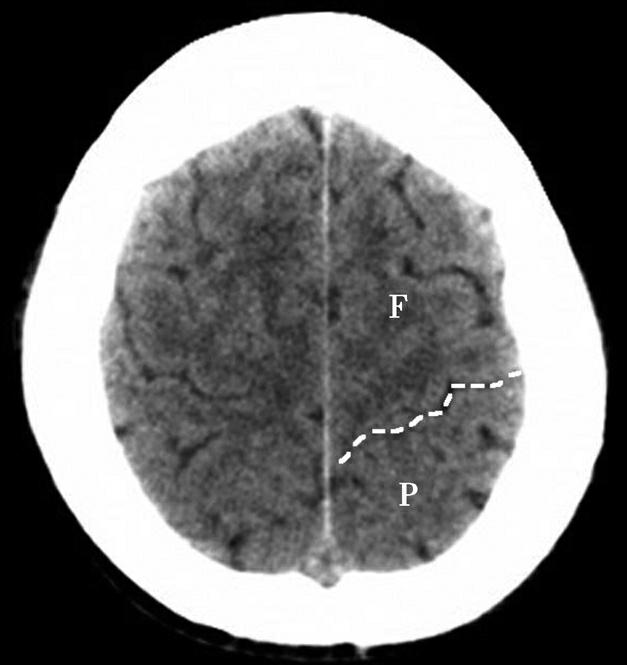

Alberta卒中项目早期CT评分(Alberta stroke program early CT score,ASPECTS)是一种评价急性缺血性卒中患者大脑中动脉供血区早期缺血性改变的简单、可靠、系统化的方法,是常用的脑卒中评定量表之一,可对缺血性病变快速进行半定量评价,有助于判定溶栓效果和远期预后。该评分主要基于CT平扫,具体分区如下(图1-2-76)所示,即选取大脑中动脉供血区2个层面。分区后共10个区域,每个区域记1分。评分时任何区域只要有低密度灶,则扣除该区域得分。正常脑ASPECTS评分为满分(10分),若MCA供血区广泛梗死累及全部区域时,则ASPECTS评分为0分。

图1-2-76 ASPECTS评分脑组织分区

A.在基底节层面(即丘脑和纹状体平面),分为各级分支M 1 、M 2 、M 3 、岛叶(缩写I)、豆状核(缩写L)、尾状核(缩写C)和内囊(缩写IC)后肢等7个区域;B.在基底节以上层面(基底节层面上2cm),包括M 4 、M 5 和M 6 。